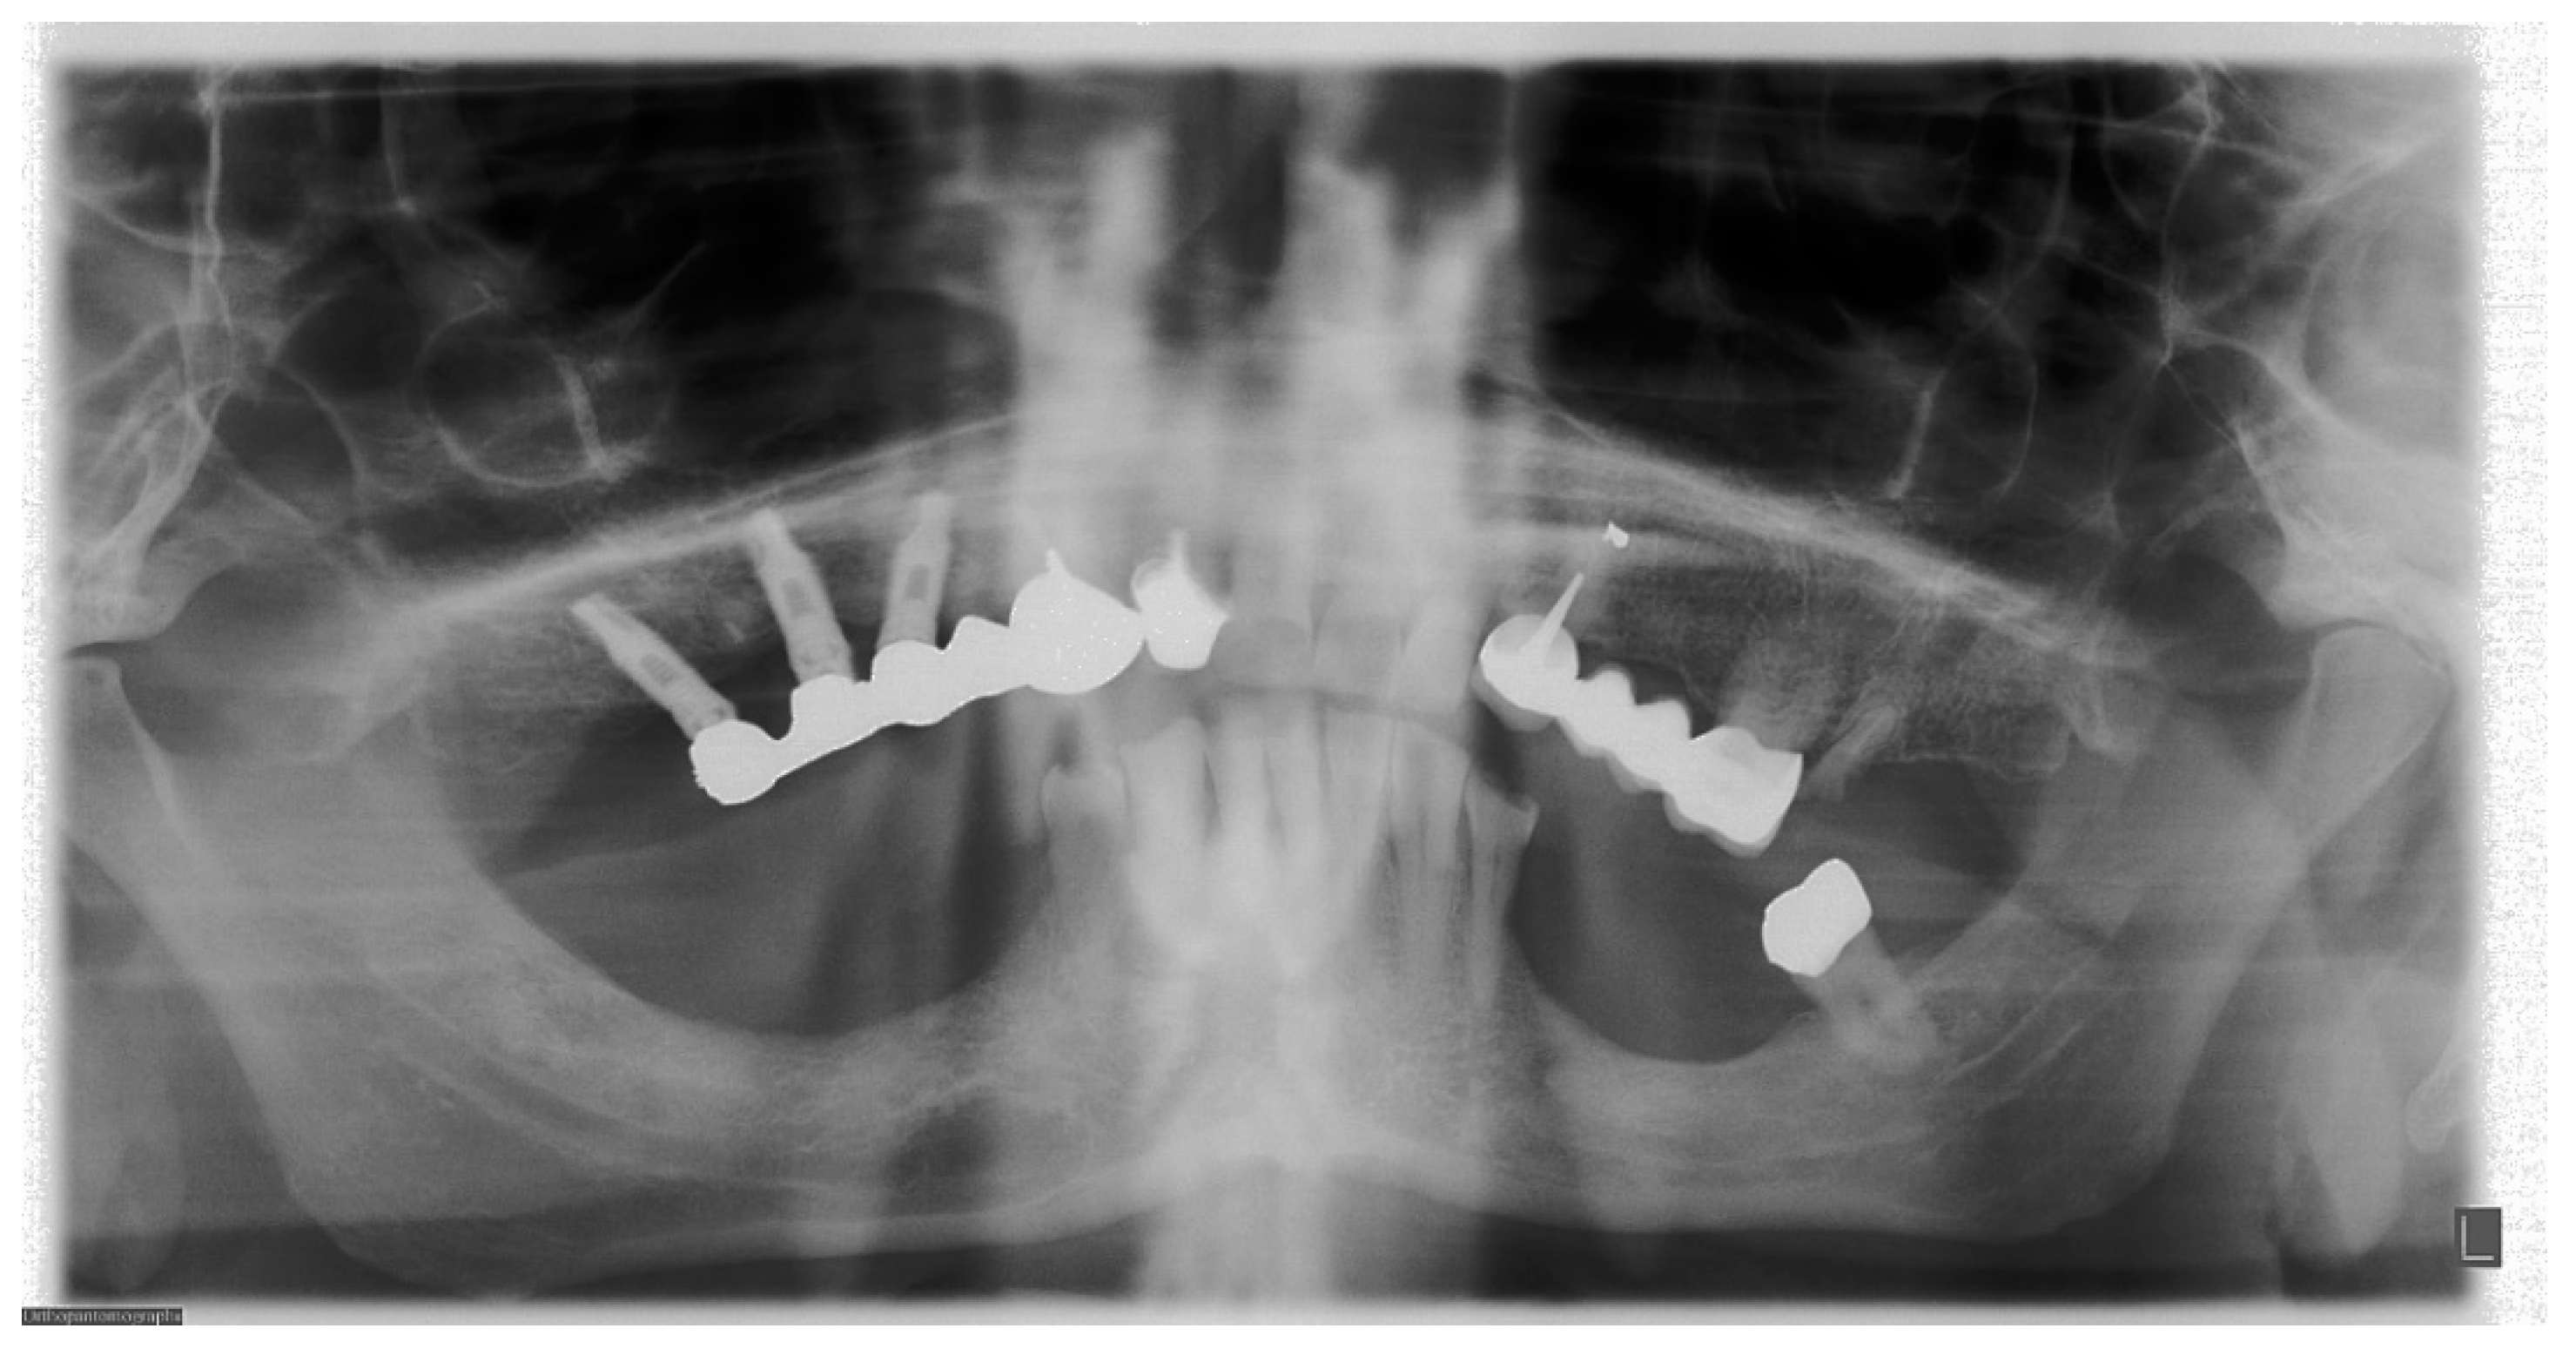

7. Metal and Motion Artefacts